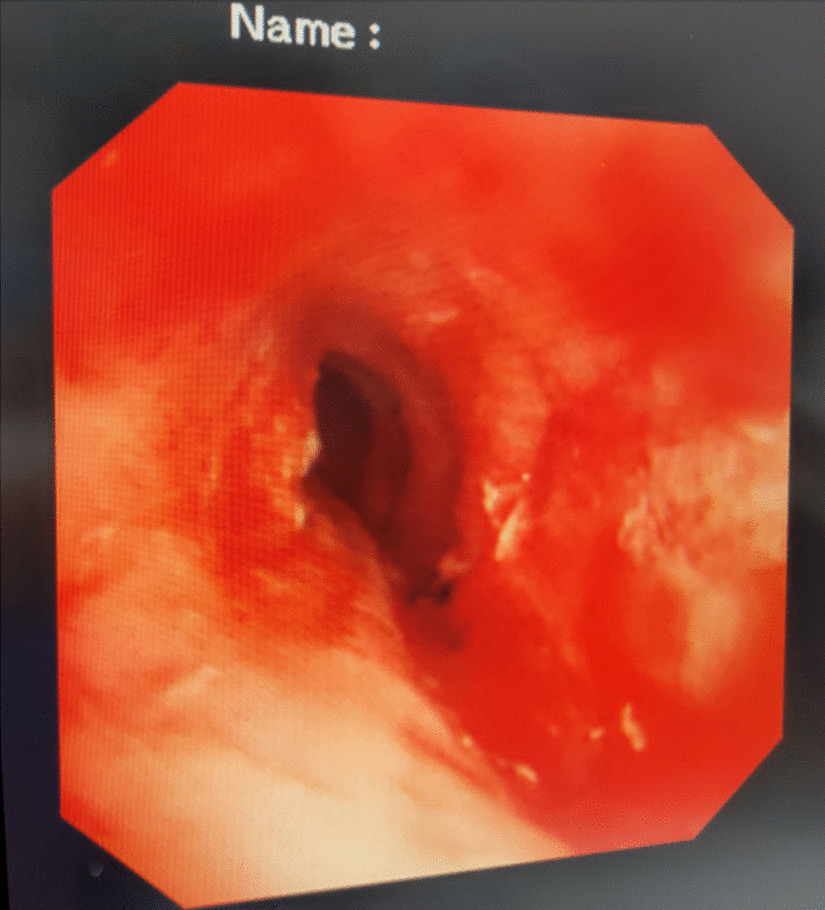

A female patient, 72 years old, was admitted for “retrosternal pain for 4 days during eating” with a healthy history before. Four days ago, the patient had a foreign body sensation in the pharynx after eating freshwater fish. Then she ate as usual but felt retrosternal pain when eating. One day ago, the pain worsened after eating rice cake and was accompanied by severe irritant dry cough without fever, hemoptysis, or hematemesis. The patient was admitted to Regional medical center for National Institute of Respiratory Disease, Sir Run Run Shaw Hospital, School of Medicine, Zhejiang University. Chest plain computed tomography (CT) scan suggested “flat esophagus and bronchial bifurcation with a high-density shadow, a foreign body was considered with the length of 2.8 cm that crossed the left main bronchial wall, and the local bronchial wall mucosa thickened” (Figs. 1, 2). Treatment was supportive with fasting, fluid infusion, monitoring and so on. During the operation, a rigid esophagoscope (S121; Hangzhou Tonglu Medical Optical Instrument Co., Ltd, Zhejiang, China) was used under general anesthesia with endotracheal tube. It was observed that the mucosa ulcer was at the 2 o’clock direction in the esophagus 26 cm away from the incisors, with hyperemia and swelling of the surrounding mucosa. No obvious foreign body was found in the cavity. Under a fiberoptic bronchoscope (BF-260; Olympus Optical Co., Ltd, Tokyo, Japan) via the endotracheal tube, a needle-shaped foreign body (considering fish bone in combination with medical history) in the proximal part and near the entrance of left main bronchus could be seen intraoperatively, and penetrated the bronchial wall. Local bronchial wall showed granulation tissue hyperplasia, mucosal swelling and easy bleeding (Fig. 3). After the granulation tissue was cleaned intraoperatively and the fish bone was exposed, the holmium laser (VersaPulse 80/100 W PowerSuite; Lumenis Ltd, Israel) with the settings of 1 J and 8 Hz was used to broke the fish bone in the middle which was located in the left main bronchus, and foreign body forceps (JHY-FG-18-120-A4; Jiuhong Medical Instrument Co., Ltd. Changzhou, China) were used to remove the two segments, respectively. There was no significant active hemorrhage in the bronchus after operation (Fig. 4). The entire operation under the fiberoptic bronchoscope lasted for 20 min. The foreign body was a sharp and hard fish bone about 3 cm in length (Fig. 5). A jejunal nutrition tube was indwelling during the operation, and nasal-feeding nutrition as well as gastrointestinal decompression were given postoperatively. Secondary infection and leakage were also monitored. No obvious leakage was noted in upper gastrointestinal contrast half a month after the operation. Then, the jejunal nutrition tube was removed, and there was no obvious discomfort when having semi-fluid food through the mouth.

Fig. 3.

A foreign body in the proximal part and near the entrance of left main bronchus is seen crossing the bronchial wall during the operation under fiberoptic bronchoscope